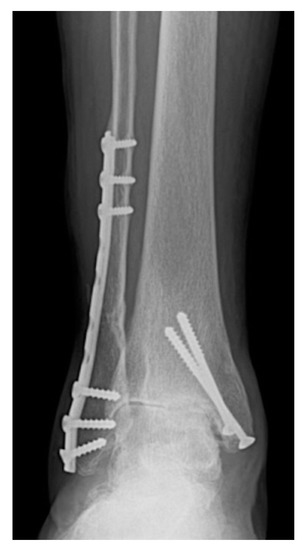

3.3. Joint Incongruence